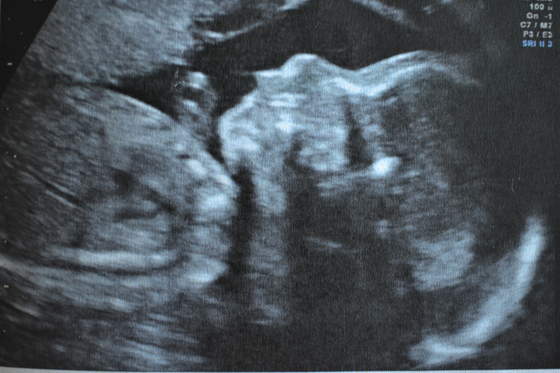

W środę udało się wykonać to echo serca maluszka, ale musiałam iść na dłuższy spacer, by młody się obrócił

Wszystko ok (serduszko i inne narządy). Waży 475 g. Rośnie. Szok, że taki duży dzieciaczek jest w brzuszku i generalnie to go przecież wcale nie czuć. Wyszły jakieś drobne ubytki międzykomorowe i międzyprzedsionkowe, ale to ponoć w trakcie ciąży lub do któregoś roku życia powinno zniknąć.

A tu nasz Adrianek: